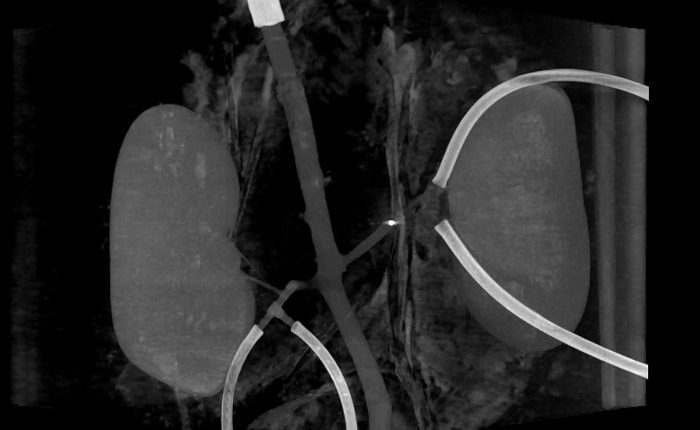

Миллиробот (яркая точка) пробивает себе путь через кровеносный сосуд

Ученые из Нидерландского университета Твенте и Медицинского центра Университета Радбауд провели успешное тестирование новой технологии по разрушению тромбов внутри кровеносных сосудов. Для этого они сконструировали специальных миниатюрных роботов, которые прокладывают себе путь через артерии. Механизмы получили название «миллироботы».

На самом деле это частный случай применения более обширной технологии, транспортной системы внутри кровеносных сосудов. Крошечные роботы напечатаны на 3D-принтере и имеют внутри постоянный магнит 1х1 мм. При воздействии внешнего магнита, который вращается в разных направлениях, робот также начинает двигаться, что и позволяет ему перемещаться внутри сосудов.

Такой робот может быть контейнером для доставки лекарственных препаратов в нужную часть организма. В варианте разрушителя тромбов он снабжен выступающими частями в форме штопора. Это позволяет роботу перемещаться против кровотока и «сверлить» сгустки крови, уничтожая их. Процедура сложная и деликатная, она требует точного управления внешним магнитом, чтобы провести миллиробота через сосуды, не повредив их.